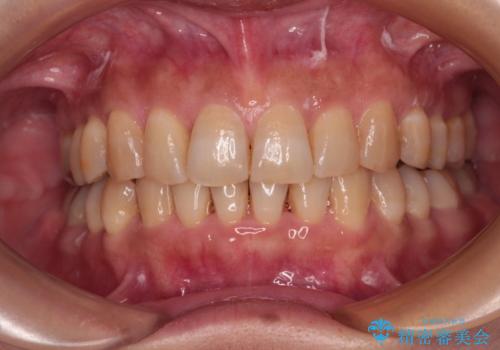

ディープバイトと前歯のデコボコ インビザラインによる矯正治療

- 前歯のディープバイトと叢生を気にして来院された患者様です。

目立ちにくい装置を希望されていたため、ワイヤー装置とインビザラインを提案したところ、インビザラインを希望されました。

下顎大臼歯が手前に倒れていたため、起き上がらせることで咬み合わせ高さを挙上し、ディープバイトと叢生を改善することとしました。